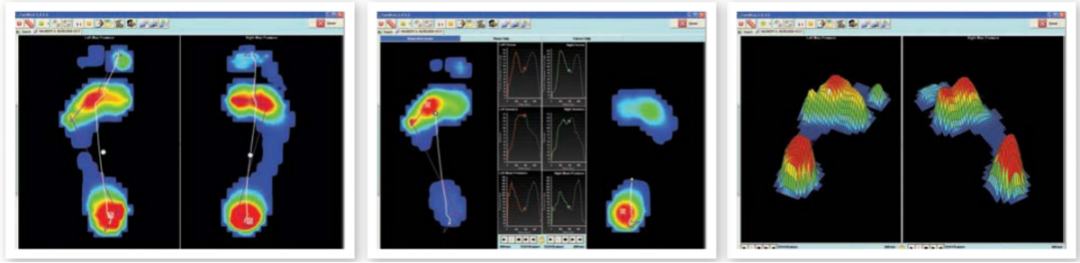

早期,人們通過“濕腳測試法”,根據(jù)腳印的形狀來判定自己的足弓類型,這也算是*早的足底壓力測量。隨著計(jì)算機(jī)和壓力傳感器的發(fā)展,足底壓力信號的準(zhǔn)確測量才得以實(shí)現(xiàn),基于各種原理的足底壓力測試系統(tǒng)也逐漸增多。

平板式足底壓力分布采集分析系統(tǒng)

美國SPI平板式足底壓力分布采集分析系統(tǒng)從遍布傳感器板的數(shù)千個微小的壓電電阻元件中捕捉足部壓力變化。就像站在秤上一樣,傳感器板記錄了現(xiàn)場壓力和壓力的臨界分布模式。

可以用于靜態(tài)、動態(tài)足底狀況和身體平衡能力的分析,被廣泛應(yīng)用于運(yùn)動生物力學(xué)研究、運(yùn)動鞋設(shè)計(jì)、步態(tài)分析、平衡分析,糖尿病足的測試、下肢骨關(guān)節(jié)疾病等臨床及科研領(lǐng)域。